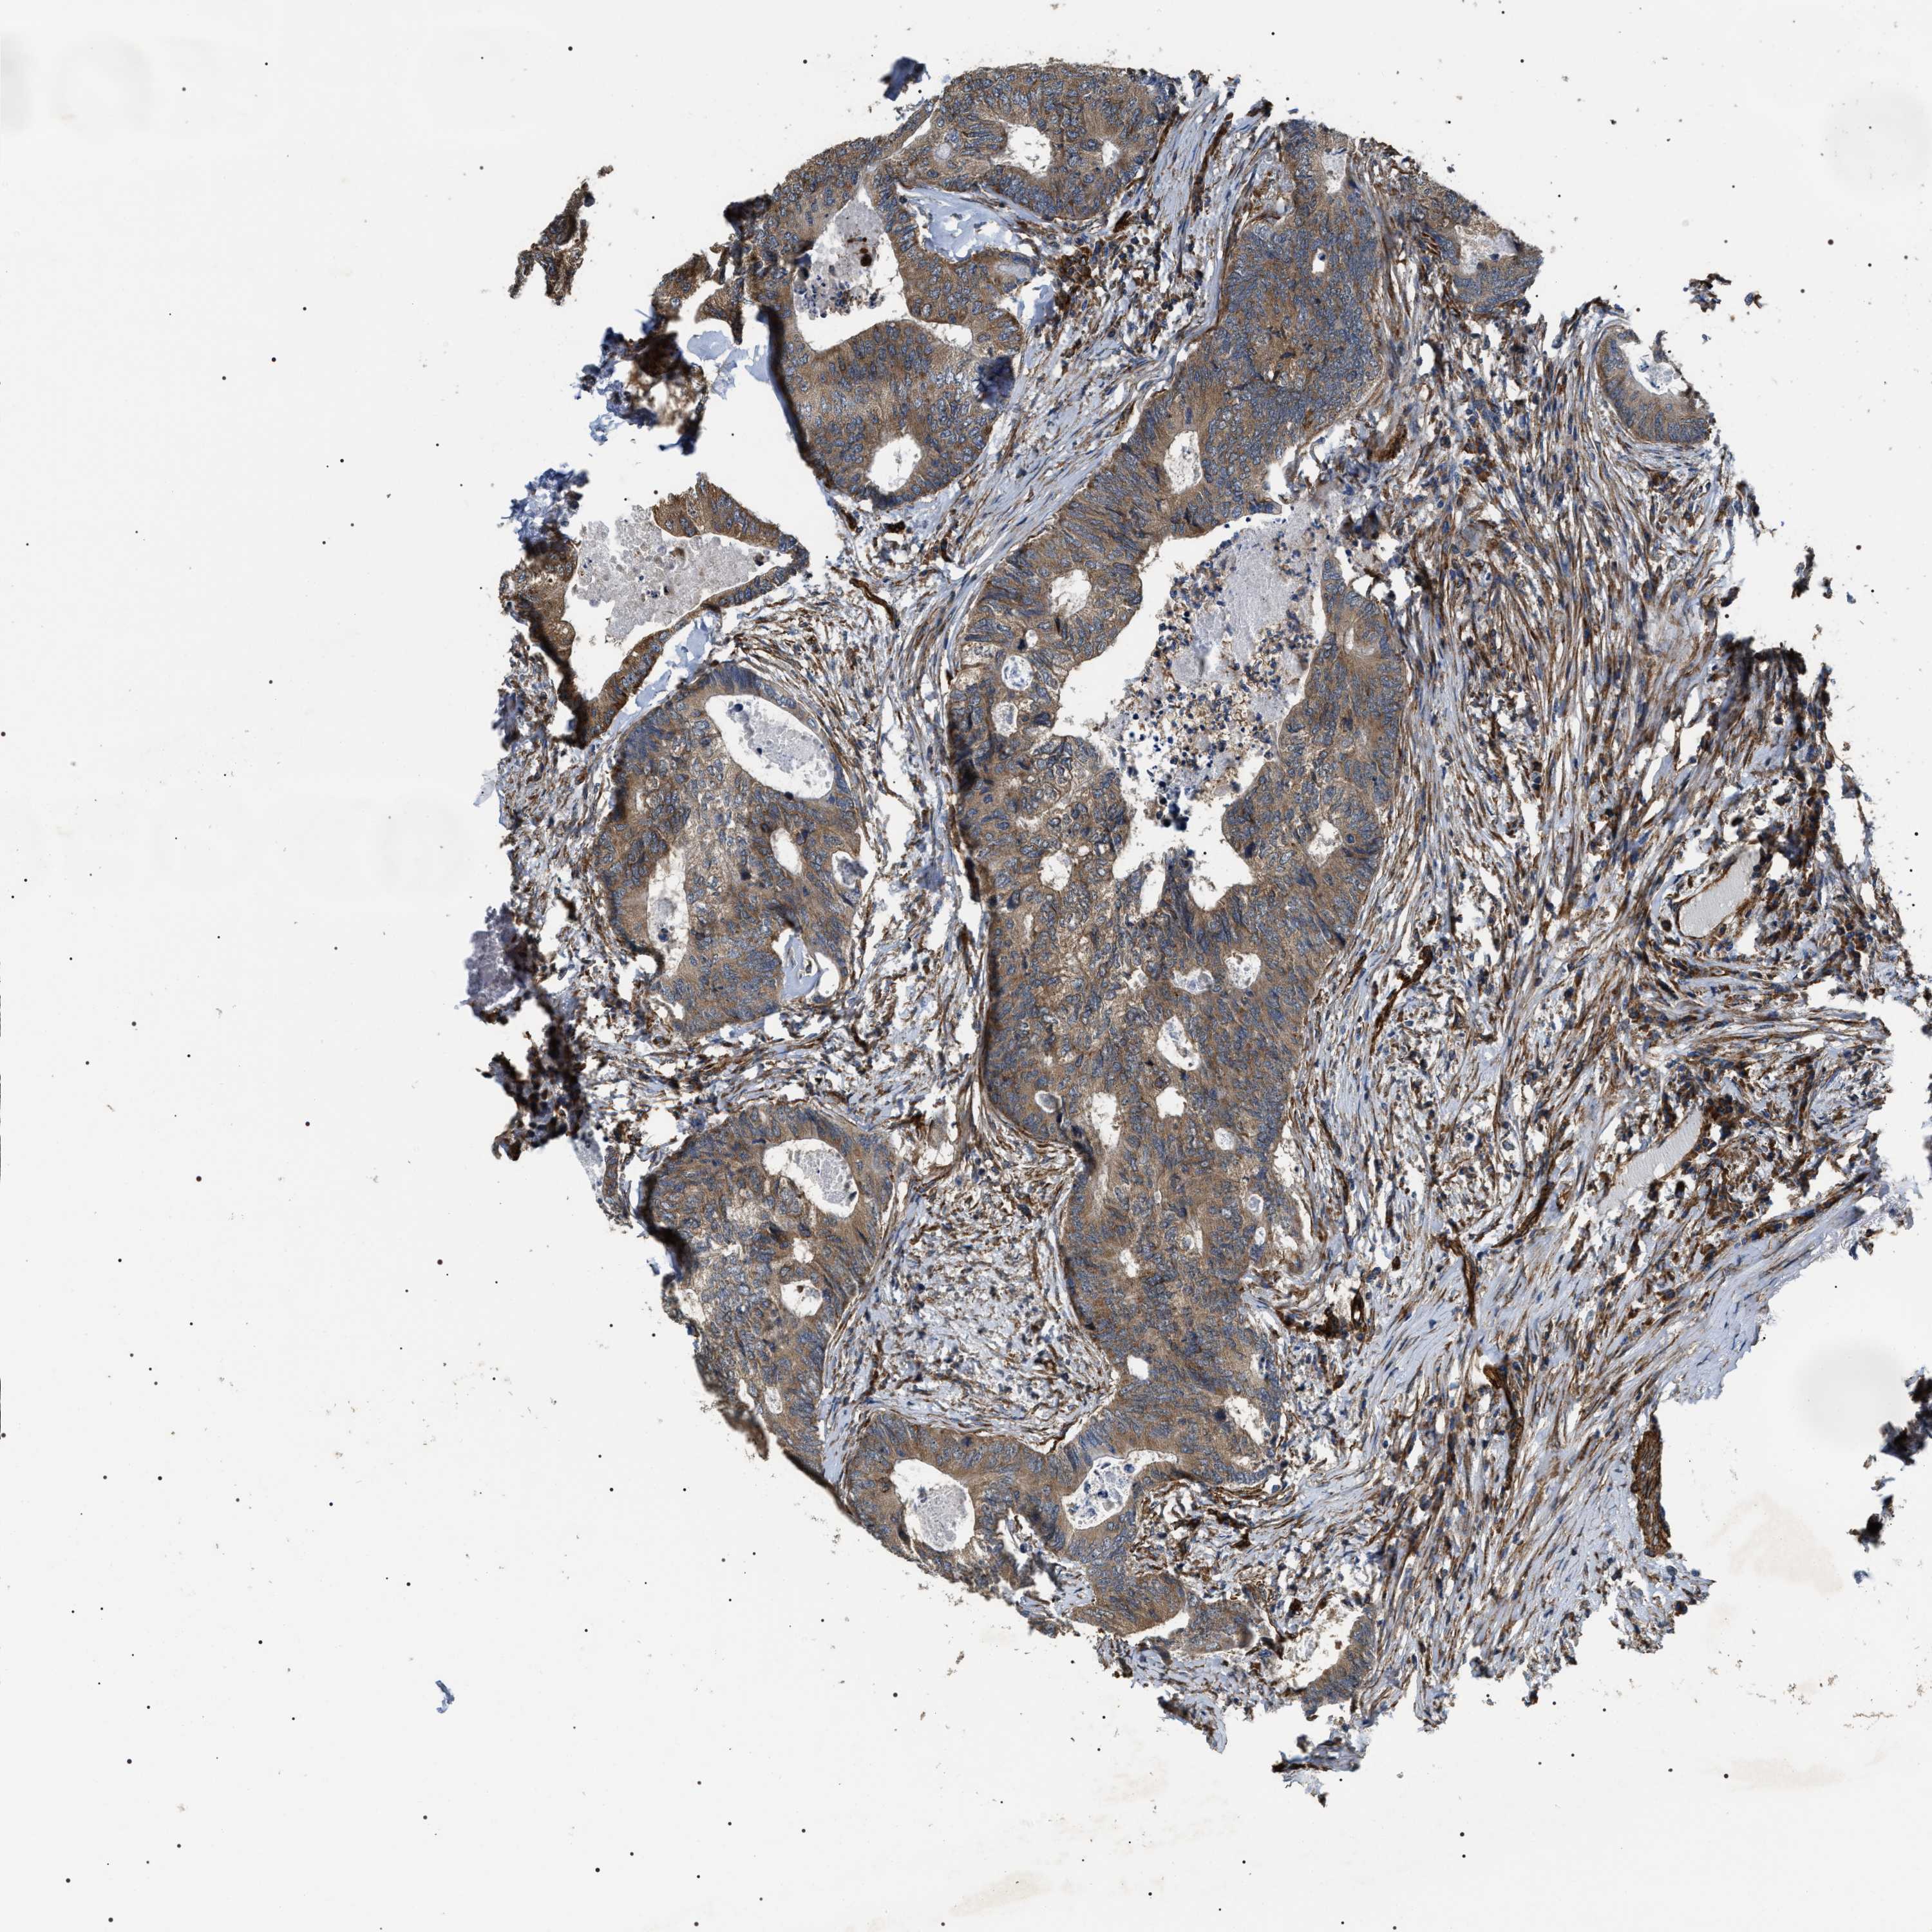

COLON ADENOCARCINOMA (VALIDATION) - Interactive survival scatter ploti

The Survival Scatter plot shows the clinical status (i.e. dead or alive) for all individuals in the patient cohort, based on the same data that underlies the corresponding Kaplan-Meier plots. Patients that are alive at last time for follow-up are shown in blue and patients who have died during the study are shown in red.

The x-axis shows the expression levels (FPKM) of the investigated gene in the tumor tissue at the time of diagnosis. The y-axis shows the follow-up time after diagnosis (years). Both axes are complimented with kernel density curves demonstrating the data density over the axes. The top density plot shows the expression levels (FPKM) distribution among dead (red) and alive patients (blue). The right density plot shows the data density of the survived years of dead patients with high and low expression levels respectively, stratified using the cutoff indicated by the vertical dashed line through the Survival Scatter plot. This cutoff is automatically defined based on the FPKM cutoff that minimizes the p-score. The cutoff can be changed by dragging the vertical line or by entering a cutoff value in the square labeled "Current cut-off".

Under the Survival Scatter plot the p-score landscape (black curve; left axis) is shown together with dead median separation (red curve; right axis). Dead median separation is the difference in median mRNA expression between patients who have died with high and low expression, respectively. It is calculated as follows: median FPKM expression of dead patients with high expression - median FPKM expression of dead patients with low expression. This is intended to aid the user in visually exploring custom cutoffs and the associated p-scores and dead median separation.

Individual patient data is displayed and can be filtered by clicking on one or more of the category buttons on the top of the page. Categories describing expression level and patient information include: high, low, alive, dead, female, male and tumor stages. The scale of the x-axis can be toggled between linear and log-scale by clicking on the "x log" button. Mouse-over function shows TCGA ID, patient information and mRNA expression (FPKM) for each patient.

& Survival analysisi

Kaplan-Meier plots summarize results from analysis of correlation between mRNA expression level and patient survival. Patients were divided based on level of expression into one of the two groups "low" (under cut off) or "high" (over cut off). X-axis shows time for survival (years) and y-axis shows the probability of survival, where 1.0 corresponds to 100 percent.

ZC3HAV1L is not prognostic in Colon Adenocarcinoma (validation)

Best expression cut offi

Based on the FPKM value of each gene, patients were classified into two groups and association between prognosis (survival) and gene expression (FPKM) was examined. The best expression cut-off refers the FPKM value that yields maximal difference with regard to survival between the two groups at the lowest log-rank P-value. Best expression cut-off was selected based on survival analysis .

When clicking on this number, the vertical dashed line indicating cut-off, the interactive survival plot, and the Kaplan-Meier curve will be adjusted to show results based on the best expression cut-off.

: 32.42

Median expressioni

Median expression refers to the median FPKM value calculated based on the gene expression (FPKM) data from all patients in this dataset. When clicking on this number, the vertical dashed line indicating cut-off, the interactive survival plot, and the Kaplan-Meier curve will be adjusted to show results based on the median expression.

: N/A

P scorei

Log-rank P value for Kaplan-Meier plot showing results from analysis of correlation between mRNA expression level and patient survival.

N/A

5-year survival highi

5-year survival for patients with higher expression than the expression cutoff.

For melanoma and glioma, 3-year survival is shown.

5-year survival lowi

5-year survival for patients with lower expression than the expression cutoff.

TCGA RNA samplesi

RNA-seq data is reported as average FPKM (number Fragments Per Kilobase of exon per Million reads), generated by the The Cancer Genome Atlas (TCGA) .

Normal distribution across the dataset is visualized with box plots, shown as median and 25th and 75th percentiles. Points are displayed as outliers if they are above or below 1.5 times the interquartile range. FPKM values of the individual samples are presented next to the box plot.

Average pTPM 28.5

Number of samples 486